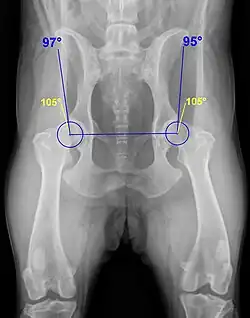

Ein wesentliches Auswertungskriterium ist der Norberg-Winkel. Er ist als der Winkel definiert, der zwischen der Verbindungslinie der Zentren der beiden Oberschenkelköpfe und dem jeweiligen vorderen Pfannenrand abgetragen wird (siehe Abbildung). Bei einem HD-freien Tier sollte er mehr als 105° betragen (gelbe Linien).[3]

Die Ausbildung der Hüftgelenke und der Norbergwinkel zeigen aber auch einige rassetypische Variationen, was bei der Auswertung durch die vom jeweiligen Zuchtverband bestallten Gutachter Berücksichtigung findet.[5]

| A | HD-Frei | In jeder Hinsicht unauffällige Gelenke, Norberg-Winkel 105° oder mehr. Manchmal noch A1 wenn der Pfannenrand den Oberschenkelknochen noch weiter umgreift. | 25 % |

| B | HD-Verdacht | Schenkelkopf oder Pfannendach sind leicht ungleichmäßig und der Norberg-Winkel beträgt 105° (oder mehr), oder Norberg-Winkel kleiner als 105° aber gleichförmiger Schenkelkopf und Pfannendach. | 33 % |

| C | Leichte HD | Oberschenkelkopf und Gelenkpfanne sind ungleichmäßig, Norberg-Winkel 100° oder kleiner. Eventuell leichte arthrotische Veränderungen. | 27 % |

| D | Mittlere HD | Oberschenkelkopf und Gelenkpfanne sind deutlich ungleichmäßig mit Teilverrenkungen. Norberg-Winkel größer 90°. Es kommt zu arthrotischen Veränderungen und/oder Veränderungen des Pfannenrandes. | 11 % |

| E | Schwere HD | Auffällige Veränderungen an den Hüftgelenken (beispielsweise Teilverrenkungen), Norberg-Winkel unter 90°, der Pfannenrand ist deutlich abgeflacht. Es kommt zu verschiedenen arthrotischen Veränderungen. | 4 % |